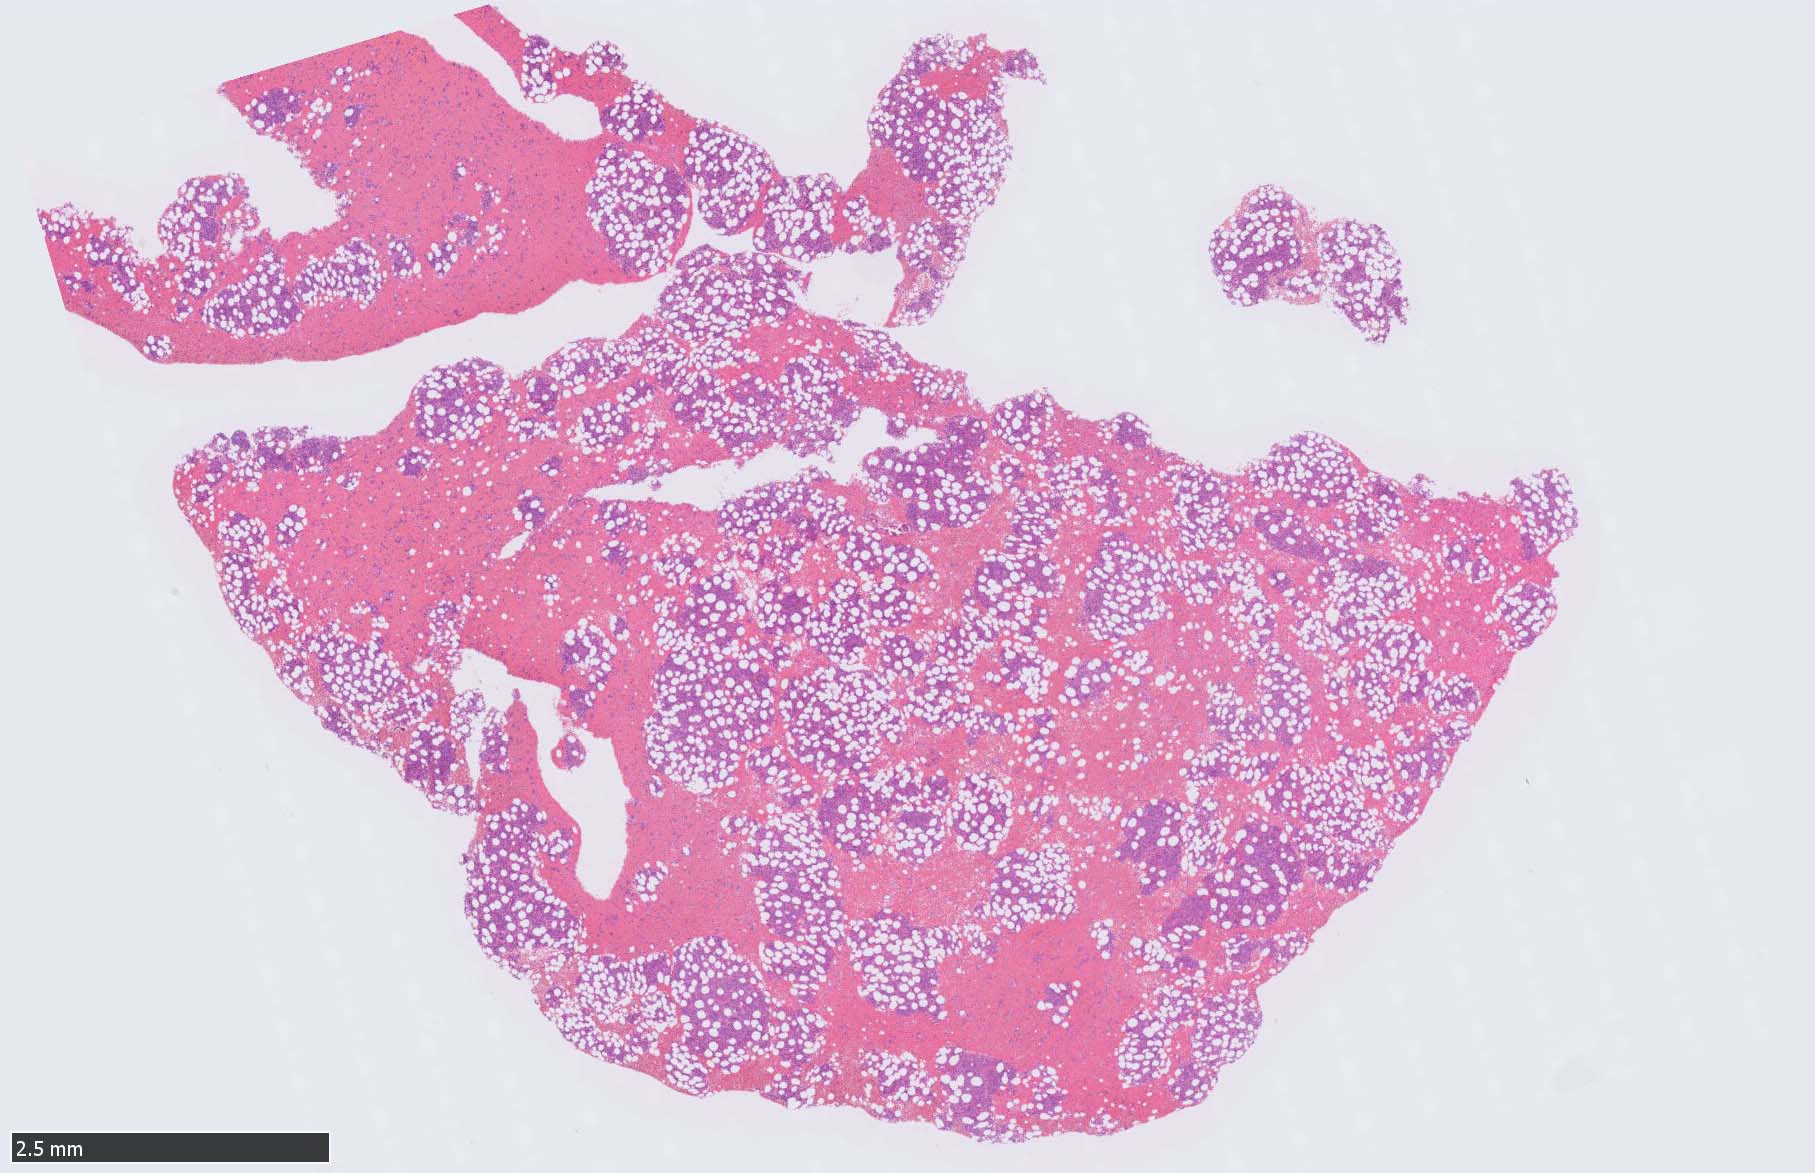

骨髄病理所見

HEでは腫瘍細胞の同定が難しい. 本症例は ASD-Giemsa染色を見ても, 腫瘍胞巣はよくわからなかった. 皮膚が先に診断がつき, 次いでBone marrowだったため, 免疫染色にすすめたが, Bone marrowが先だと診断に困ったかもしれない.

免疫染色

CD4は染まりすぎの感がある(濃く染まる細胞はCD4+ T-cellかもしれない). CD56, CD123が陽性で可能性が高くなり, BPDCNの診断にはCD34は陰性であることが必要

症例骨髄に認められた異形成造血所見

Mgkは低分葉, 円形単核の細胞が多く, 分離円形核のMgkもみられた. 赤芽球はproerythroblstsのみの小集簇や孤在性出現あり. 成熟赤芽球が乏しい. 顆粒球系細胞も分葉好中球への分化像が少ない.

免疫染色では, HbFを発現する赤芽球の集簇巣が散見しているほか, p53陽性細胞が軽度に増加している. CD34陽性細胞増加はなし.CD42b染色でmicroMgkはみられなかった. 異形成造血が強く疑われる.